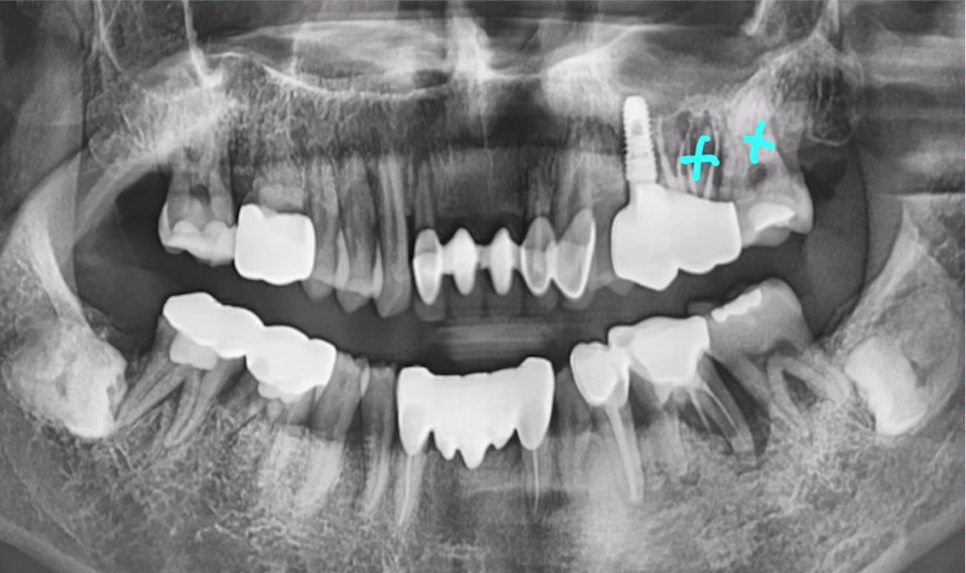

"오른쪽 아래 어금니가 아파요" 하고 오신 환자분이신데요.

CT 촬영 결과 안쪽 뼈는 양호했지만, 바깥쪽 뼈는 매우 얇은 상태였습니다.

이 경우 무리하게 당일임플란트를 진행하면 뼈 흡수나 식립 실패 가능성이 크죠.

그래서 저는 발치 후 즉시 심지만 안쪽으로 깊게 심어드렸습니다.

안쪽 뼈는 외측보다 뼈 흡수가 덜 되고, 밀도도 더 높은 경우가 많기 때문에

임플란트를 안쪽으로 깊게 심어 고정력을 더 확보했습니다.

임플란트 식립 이후 뼈도 잘 차오르고, 예후도 좋은 모습을 볼 수 있습니다.